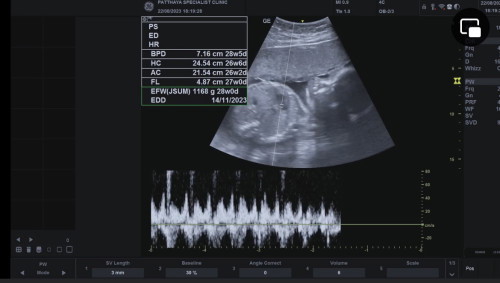

มีบ้านไหนน้ำหนักน้องเกินเกณฑ์บ้างคะ บ้านนี้พึ่งไปหาหมอมา 25w น้ำหนักน้อง 1168 น้ำหนักแม่ตั้งแต่ท้องขึ้นมา 1.2 โล หมอบอกน้องอ้วน น้ำหนักเกินไป 2 อาทิตย์ คือดีหรือไม่ดีคะ ต้องลดอาหารไหมคะ #ขอบคุณสำหรับคำตอบค่ะ #ท้องแรก